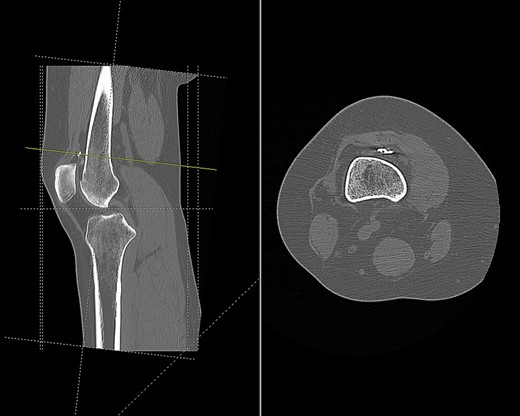

CT scan of the right knee showing perforation of anterior femoral cortex (sagittal and axial view).

Based on tunnel positions, we conclude that the original surgeon had perforated the anterior femoral cortex when drilling from the medial femoral condyle. Due to this an anterior cortex endobutton fixation was used to supplement the medial condylar interference screw fixation. A degree of likely soft tissue interposition in the suprapatellar region led to migration of the endobutton, and subsequent rupture from its scar tissue bed following minimal trauma.